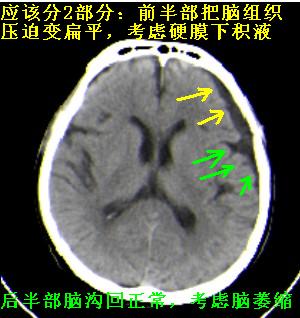

本例左侧额颞部内板下新月形低密度影分布,邻近脑组织轻度受压;脑萎缩应该有脑沟相对宽深的表现,而本例病人额叶的脑沟是受压闭塞的。所以考虑为硬膜下积液。

以下是引用yemin92007在2006-11-13 9:02:00的发言:[br]本例左侧额颞部内板下新月形低密度影分布,邻近脑组织轻度受压;脑萎缩应该有脑沟相对宽深的表现,而本例病人额叶的脑沟是受压闭塞的。所以考虑为硬膜下积液。

1.左额颞顶区硬膜下积液

2. 脑萎缩